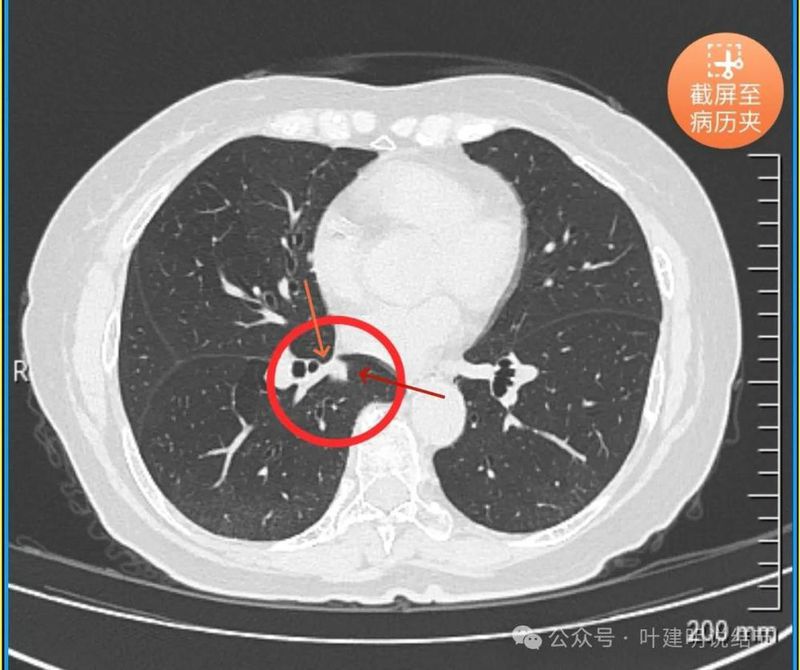

再看2024年5月时复查的影像:

分叶,混合偏实性密度,血管贴边走行。

与支气管紧贴,黄色箭头所示处似乎支气管壁与病灶已经愈着。

上图又见结节与支气管不是都愈着的,说明侵袭性并不强,病灶表面光滑。

天蓝色箭头所指处是北段支气管与病灶之间,感觉较2月份贴得近了一点点。病灶表面仍是光滑的,总体感觉有膨胀性。

病灶边缘光滑,有血管穿出来似的。

表面光滑,有膨胀性。

内部密度较为均匀,就位于肺门部。

边缘光滑,实性,有膨胀感。

与血管关系近。

边缘区域与下肺静脉间隙不太清楚。